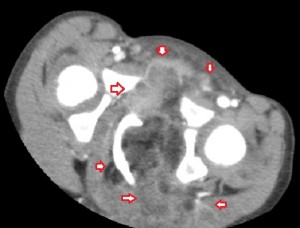

All the images in the lower panel are MR images (from left to right, axial unenhanced T1; fat-suppressed T1 post-gadolinium; coronal T1 without fat suppression; fat-suppressed sagittal T2). They show the extent of the disease better than CT and confirm that it is primarily lipomatous with little soft-tissue content. It infiltrates most of the left gluteal muscles, occupies the entire left perineum and ischiorectal fossa, and extends proximally in the retroperitoneum to the level of the sacral promontory.